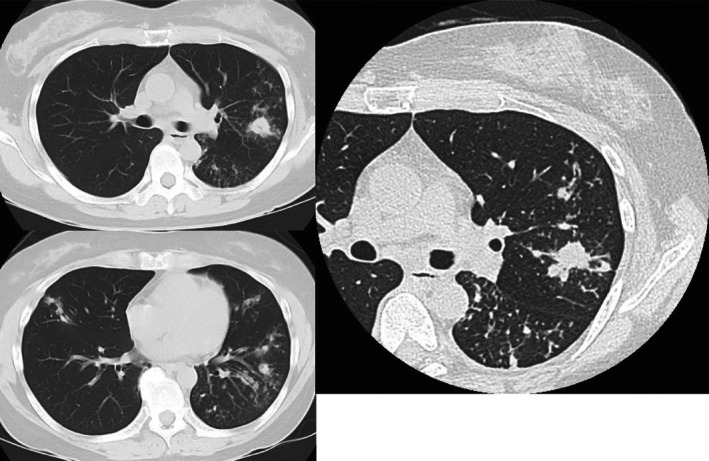

气管支气管结核是一种在治疗慢性咳嗽患者时需要特别注意的疾病,例如支气管哮喘患者。

Tracheobronchial tuberculosis is a disease that requires careful attention when treating patients with chronic cough, such as those with bronchial asthma.